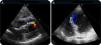

Case reportA 76-year-old woman with no previous history of cardiac disease, dyslipidemia as a cardiovascular risk factor and no other medical conditions presented with intermittent chest pain for four hours compatible with angina. She denied previous symptoms of similar characteristics. On admission, her blood pressure was 105/60 mmHg and heart rate was 90 bpm, and she reported mild persistent pain. The ECG showed complete absence of R waves and ST-segment elevation in leads V1–V2 (Figure 1). Physical examination revealed no abnormalities except for a systolic murmur (III/VI) on the left sternal border and mesocardium. Hand-held echocardiography showed no significant pathologic flows, although the patient's clinical situation made it difficult to carry out a complete assessment. She was immediately referred to the catheterization laboratory for percutaneous coronary intervention (PCI).

Coronary angiography showed no coronary lesions or signs of partially dissolved thrombus, and coronary flow velocity was normal (Figure 2). The septal branches from the left anterior descending and posterior descending arteries were reviewed carefully, but missing branches, significant atherosclerotic plaques or signs of ostial occlusion were ruled out. Ventriculography, performed to assess wall motion abnormalities, showed a VSD (Figure 3A and B and Online Video 1). Intravascular ultrasound was not performed given the progressive worsening in the patient's clinical situation and evidence of septal rupture after ventriculography. She was transferred to the coronary care unit for clinical stabilization before surgical repair. Transthoracic echocardiography (TTE) confirmed the presence of a 7 mm dissection involving the apical third of the septum (Figure 4A and B). Initially, a direct through-and-through defect resembling a simple rupture was observed (Online Video 2). However, additional images suggested a possible complex rupture with dissection tracts opening to the right ventricle in its mid segment (Online Videos 3 and 4). Initial measurements of cardiac troponin I and creatine kinase were 6.3 ng/ml and 267 IU/l, respectively, slowly decreasing in subsequent analyses. The patient's clinical condition progressively worsened, requiring inotropic support and intra-aortic balloon counterpulsation before emergency surgical patch repair.